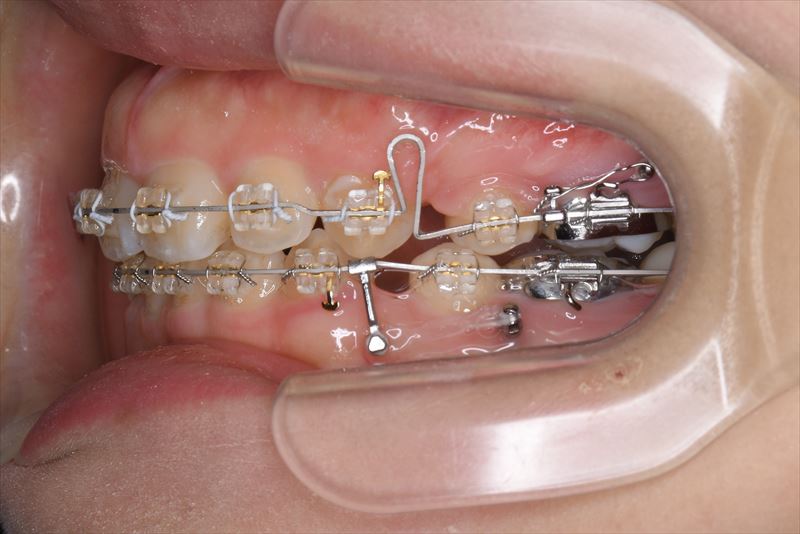

治療中

- 治療に用いた主な装置

- マルチブラケット装置、アンカースクリュー

- 上顎両側4番、下顎右側5番、下顎左側4番抜歯

- 口唇の突出を気にされて来院いたしました。Eラインより口唇の突出、オトガイ部の緊張を認めました。アンカースクリューを用いて前歯の牽引を行うことによって良好な側貌となりました。治療途中で遠方に引っ越されたため来院が困難となり治療期間が延びてしまいましたが、患者様のご協力もあり無事に治療を終えることができました。